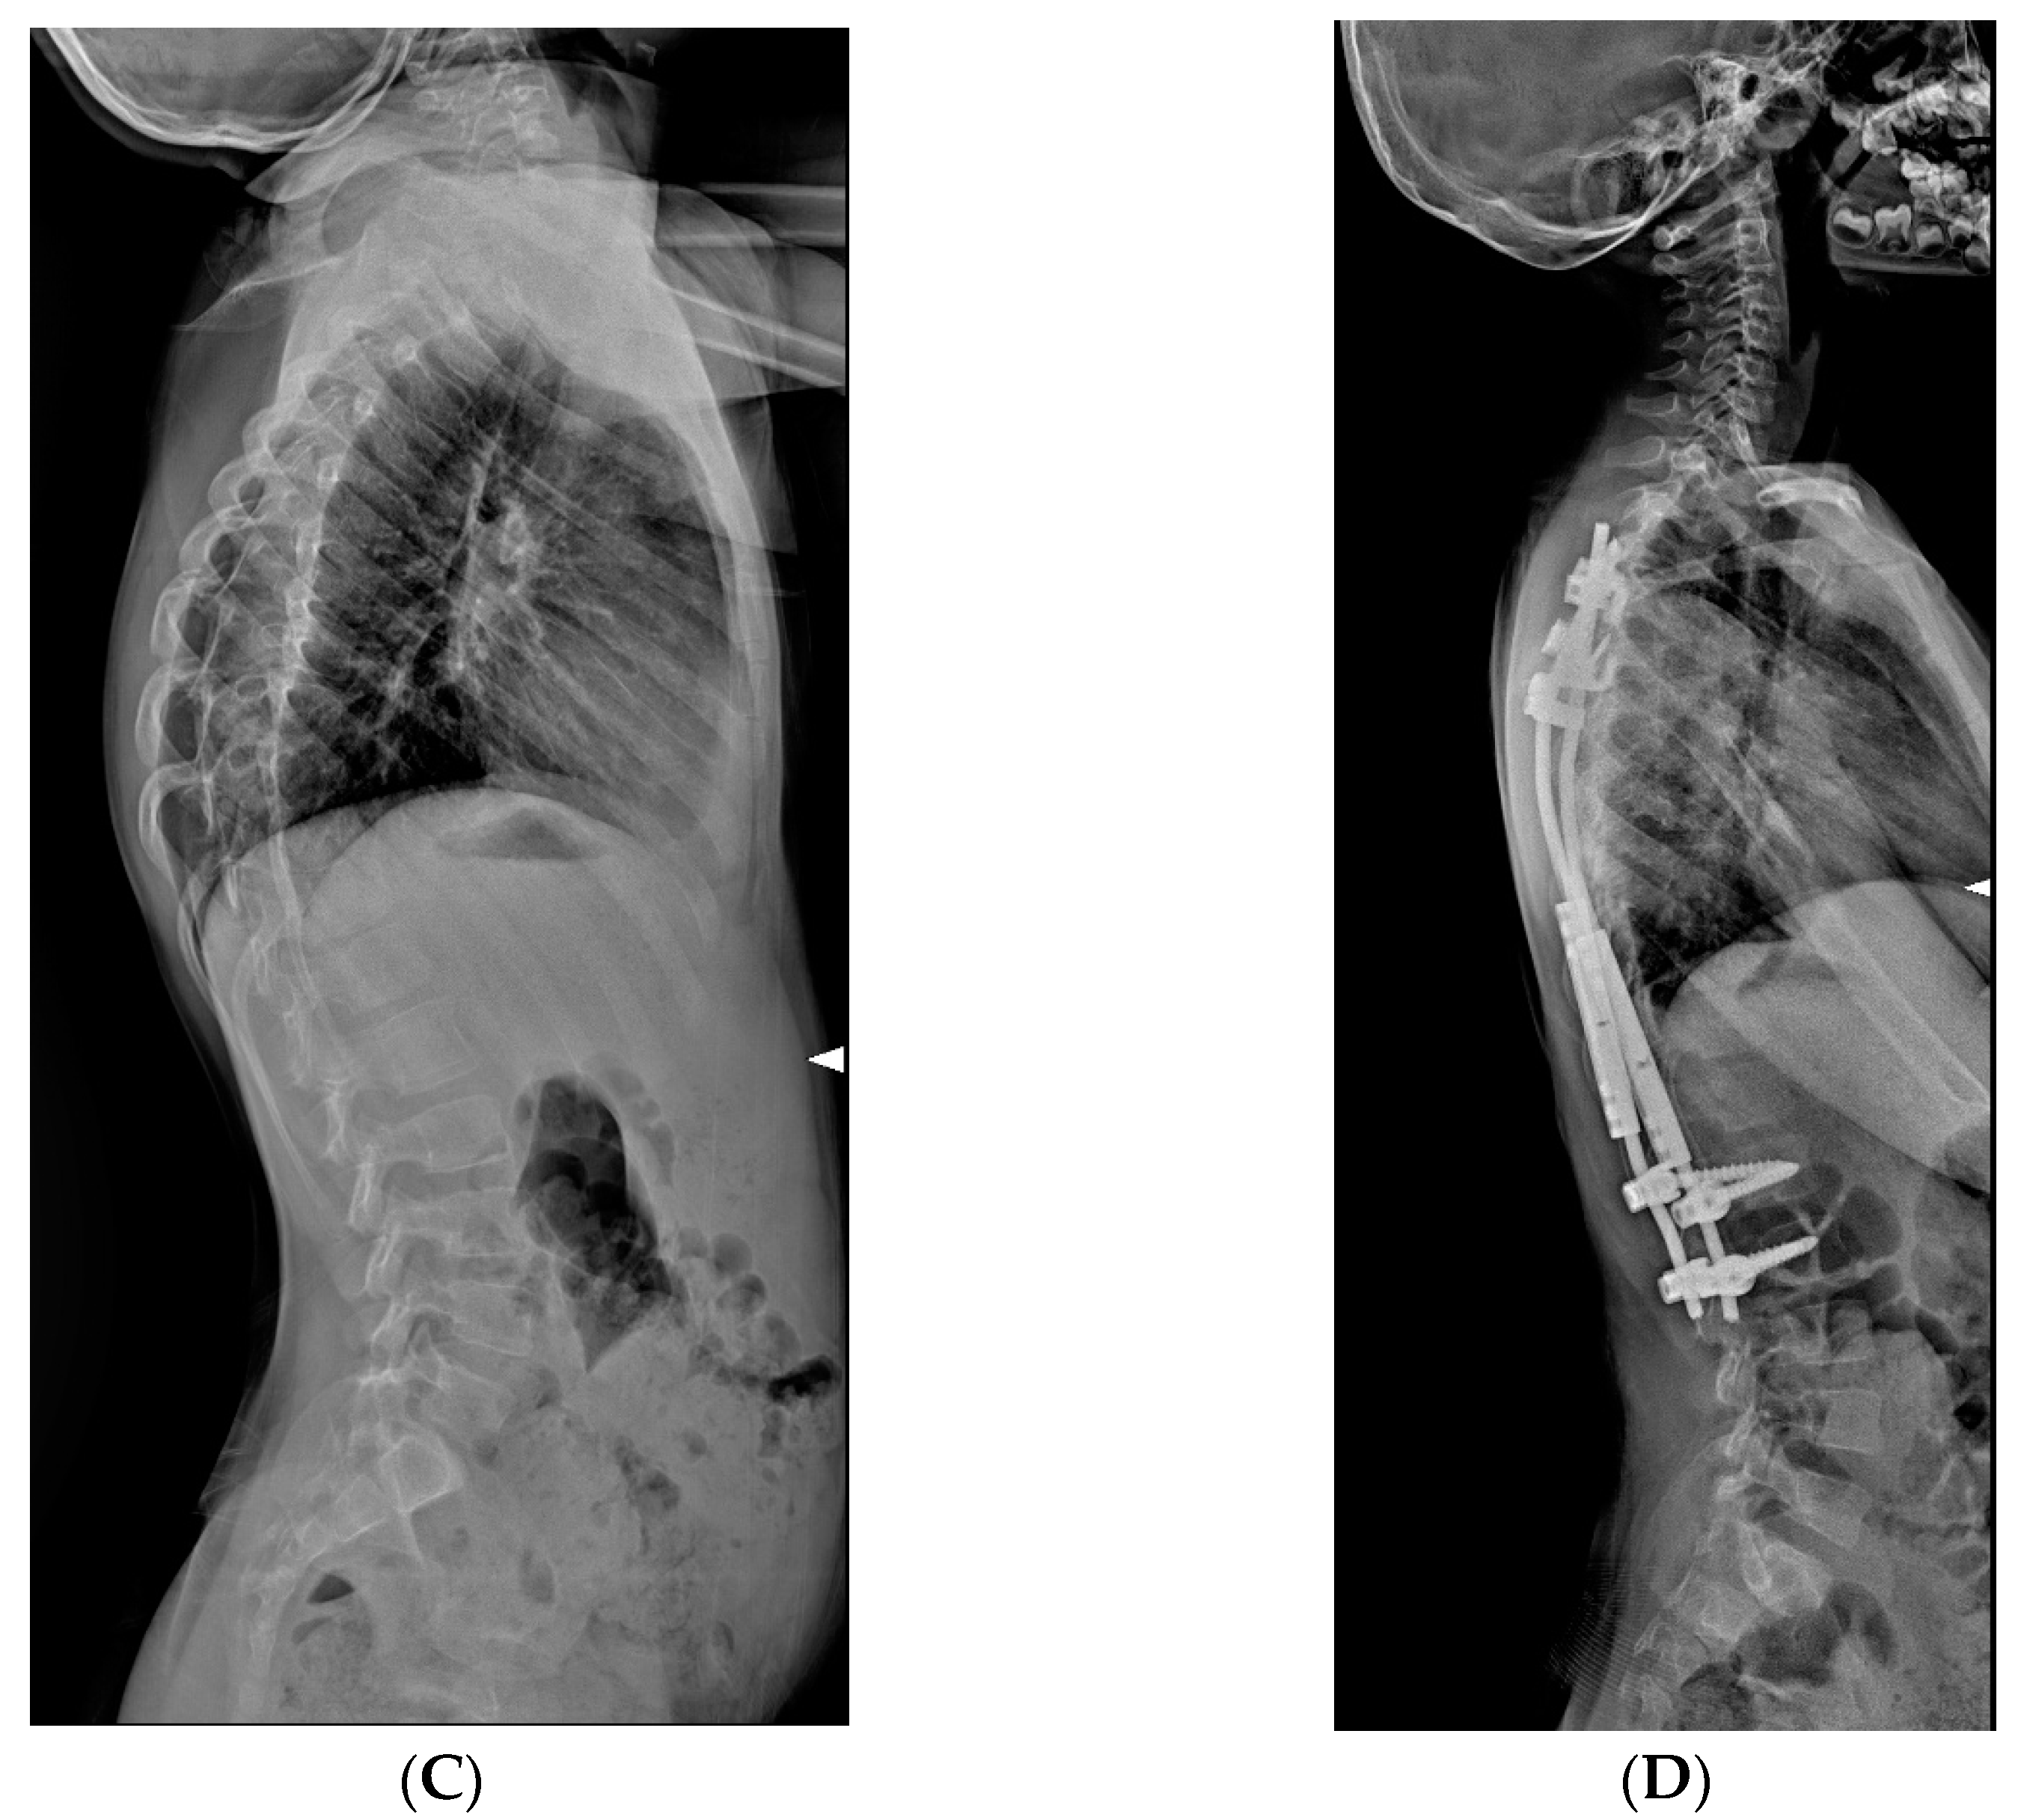

Figure 4.

X-Rays of early onset scoliosis (EOS) corrected with magnetically controlled growing rods (MCGR): (A) pre-operative antero-posterior X-ray view; (B) post-operative antero-posterior X-ray view; (C) pre-operative lateral X-ray view; (D) post-operative lateral X-ray view.

MCGR are distraction-based systems without the need for repeated surgery; they can allow growth with remote control through an externally placed device to distract the rod via a magnetically driven linear actuator [10,11], on average, every two months. Theoretically, this device can diminish the complications of infection and lack of soft-tissue coverage. It may be especially helpful in children with comorbidities that make the repeated surgeries required by the usual distraction methods particularly difficult (Figure 3 and Figure 4). MCGR involved the same surgical technique as TGR, with the difference that the bar had a magnetic telescopic connector, which was lengthened transcutaneously. Despite the advantage of not requiring multiple surgeries, MCGR systems require more frequent lengthening, approximately every 2 months. We should point out that MCGR corrected partially the sagittal deformity, since the distraction actuator area cannot be contoured as in the TGR construct.